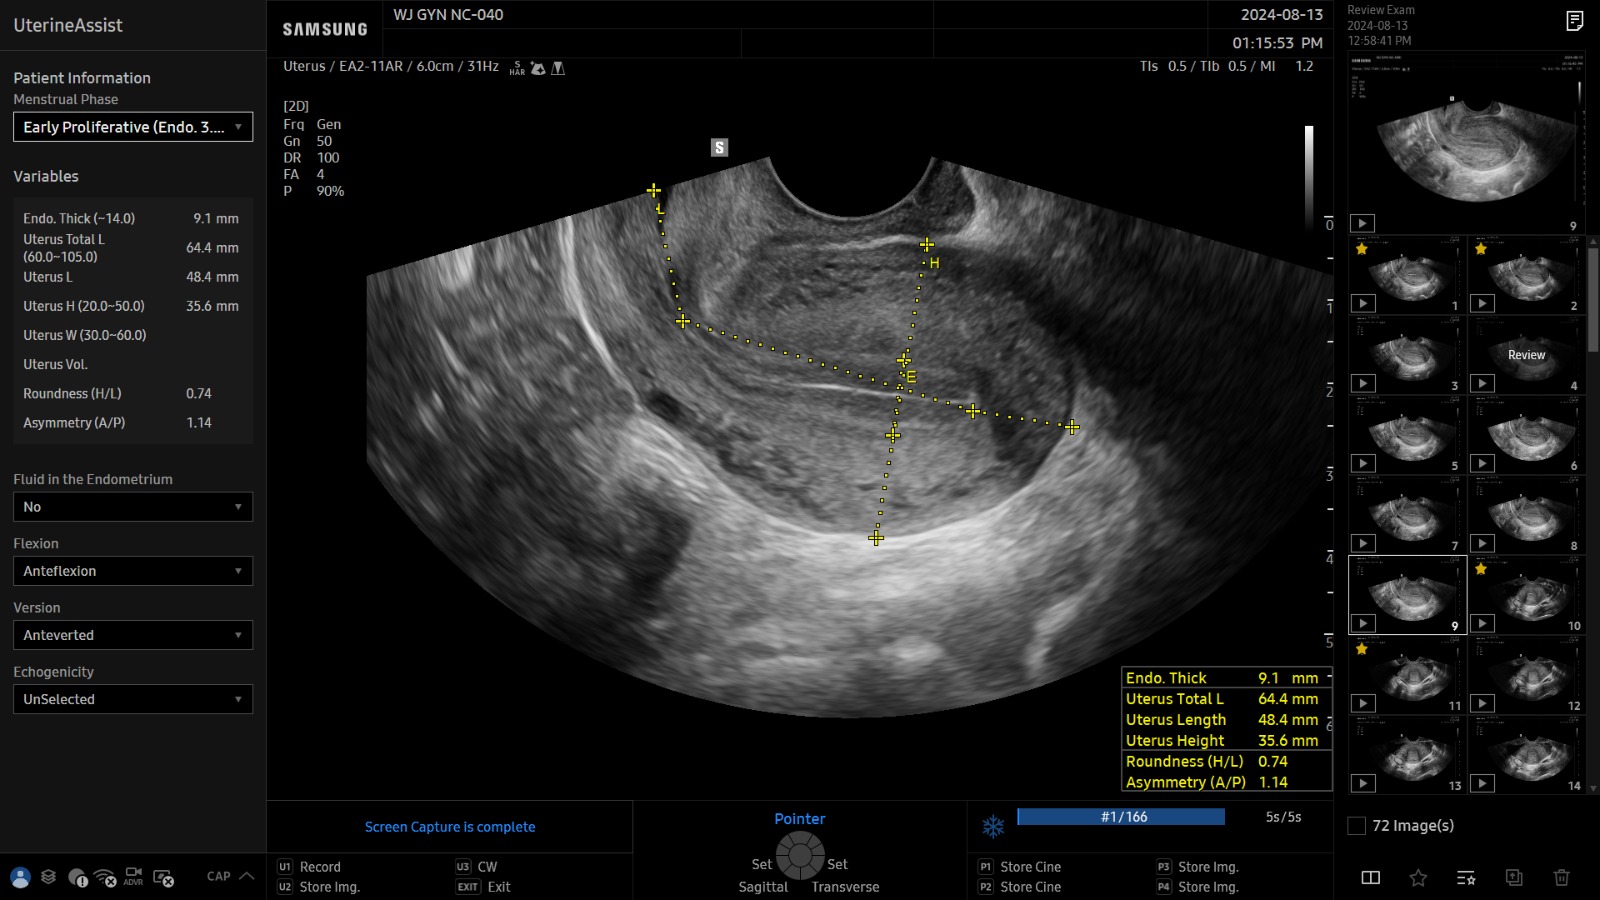

L’outil UterineAssist™, basé sur la reconnaissance d’image, permet en un clic de mesurer automatiquement la taille et la forme de l’utérus, facilitant ainsi la détection d’anomalies.